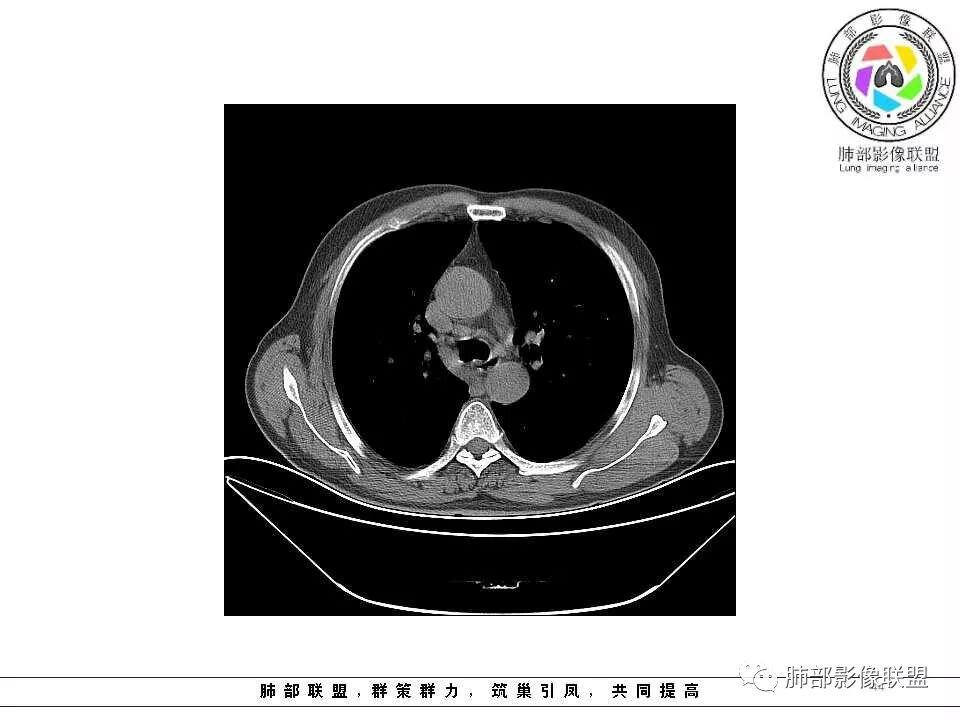

纵隔窗上似乎结节内可见点状高密度影,同时没有明显肿大淋巴结

左肺上叶光滑结节影 似乎与支气管没有关系  ,给的纵隔窗病灶中心似乎点状钙化  病灶旁有更小结节,与上一年片比较 结节增大明显  考虑恶性 类癌可能

肺气肿背景,2016年左肺上叶上舌段见微结节,2017年5月左肺结节增大,密度均匀,边缘光滑锐利,与邻近血管关系密切,血管贴壁走行,外侧见尖状突起,下舌段片状影,沿着支气管走行,内有粘液栓,考虑鳞癌,鉴别小细胞肺癌。

肺气肿背景,2016年左肺上叶上舌段见微结节,一年后左肺结节增大,密度均匀,边缘光滑、膨隆,似见小分叶,下舌段片状影,沿着支气管走行,内,老年患者,咯血1月。考虑恶性病变并阻塞性肺炎,鳞癌?注意鉴别结核。

左肺上叶舌段支气管管壁略增厚 间隔一年 管壁增厚明显 向腔外突出形成结节 管腔闭塞 远端片状及斑片影 纵隔淋巴结增大 肺气肿背景 考虑鳞癌伴阻塞性炎症可能

老年男性,肺气肿背景,左肺上叶舌段一年前小结节后长大,实性,与邻近气管关系密切,远端有少许小片状炎症类小结节状,左肺门淋巴结肿大,首先考虑恶性,鳞癌可能性大,代排小细胞癌。病灶下方斑片状影,考虑炎症。

老年男性,肺气肿背景,对比前片,左肺上叶舌段结节较前进展,周围有斑片状条状密度增高影,左肺门淋巴结肿大,有咯血史抗炎后效果不佳,目测增强强化不好判断,考虑肺癌并阻塞性肺炎可能,鉴别炎症性肺癌,真菌类肺炎,肺脓肿,肺结核,建议完善肿瘤标志物,结核相关检查,病原体检查。

@南边 我觉得最关键的是两个问题,一是腔内堵塞这个结节的纵隔窗看不到,所以到底是不是结节样肿物不明确,第二个就是没有增强,这个腔内病变与周围结节的强化性质是否一致,强化程度及强化曲线如何?